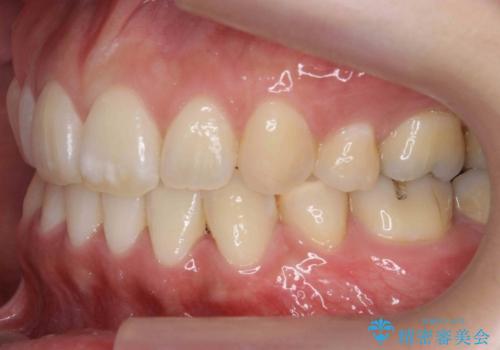

真ん中が右にずれている 前歯のがたつき 治療途中に地方へ引っ越したが、通ってワイヤー矯正

- 前歯のがたつきを主訴に来院。

前歯のクロスバイト、上の前歯の正中が右にずれていました。

右上の奥歯の高さもない状態でしたが、矯正治療が終わってからしっかりかぶせました。